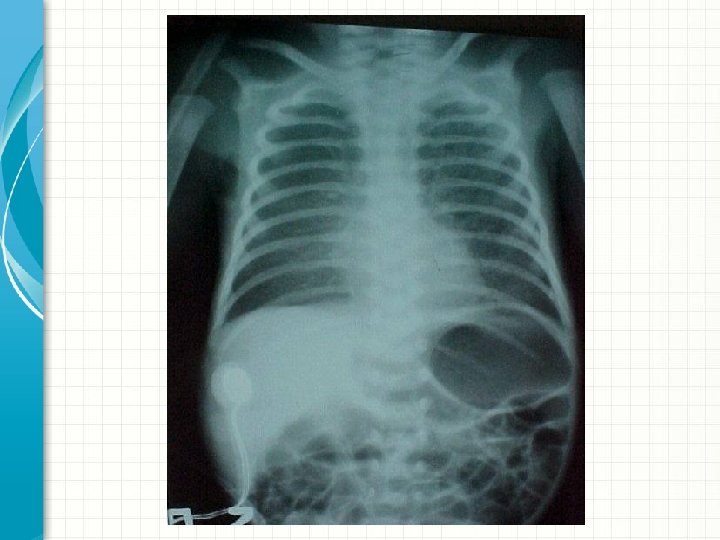

RX de tórax 4 h DV – antes do surfactante

RX de tórax 8 h DV – após surfactante